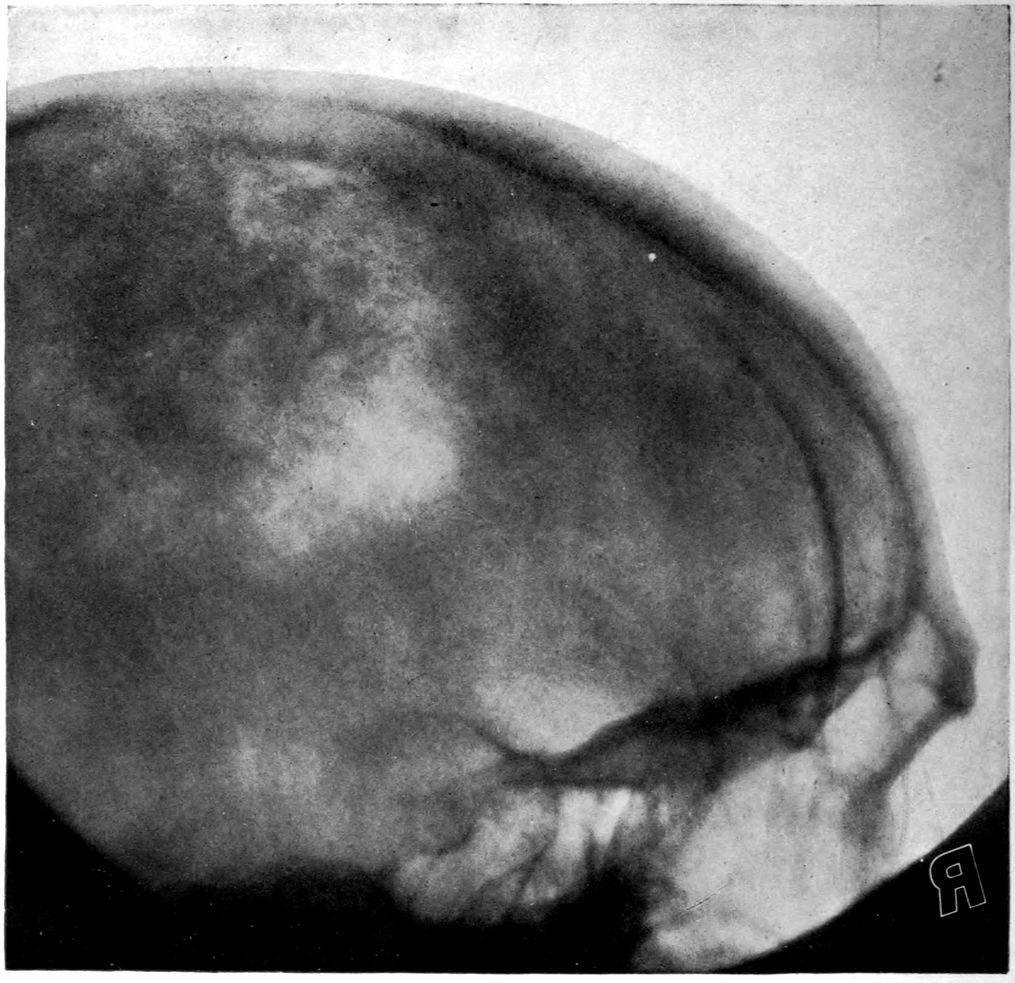

Case 4. James Pierce was an almshouse transfer to the Danvers Hospital in his fiftieth year. He died three years later. The accompanying brain pictures demonstrate so extensive a lesion of the left hemisphere that it is of great interest to determine if possible the genesis and course of his disease. It appears that syphilis had been acquired somewhere about the age of 38 or 40, so that the total duration of the process was between 13 and 15 years. In Pierce’s forty-third or forty-fourth year, he had a shock while walking in the streets of his native city, whereupon he was subsequently transferred to the Danvers Hospital, whose data have been summed up as follows (we are obliged to Dr. Charles T. Ryder for these data):

Head: Calvarium of moderate thickness; diploë present; dura slightly adherent over bregmatic region. Longitudinal sinus contains cruor clot. Dura is somewhat thickened and slightly more opaque than normal. Pacchionian granulations, small but fairly numerous. Pia contains throughout a considerable excess of clear 44serous fluid. The convolutions in general are of good breadth and proportion. There is an atrophic area roughly circular in outline and about 2 cm. in diameter in the posterior part of the right third frontal convolution corresponding to Broca’s area on the opposite hemisphere. The space thus formed is filled with edema held by the pia. On the left side is a similar subpial collection which covers the site of the posterior portions of all of the third frontal convolutions, parts of the lower end of the precentral convolution, and the whole of the first temporal convolution, which have disappeared entirely. The basal vessels show slight changes.

Vascular neurosyphilis—effects of syphilitic thrombosis of Sylvian artery 10 years before death. (Case 4.)